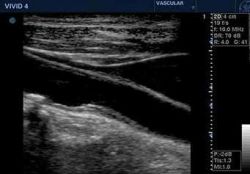

Bei Gefäßuntersuchungen handelt es sich meistens um sogenannte dopplersonographische Diagnostik. Hierbei kann man die Fliessgeschwindigkeit des Blutes messen, die bei verengten Gefäßen besonders hoch ist. Im Duplexverfahren lassen sich diese Veränderungen auch im Bild darstellen. (siehe Abbildung)